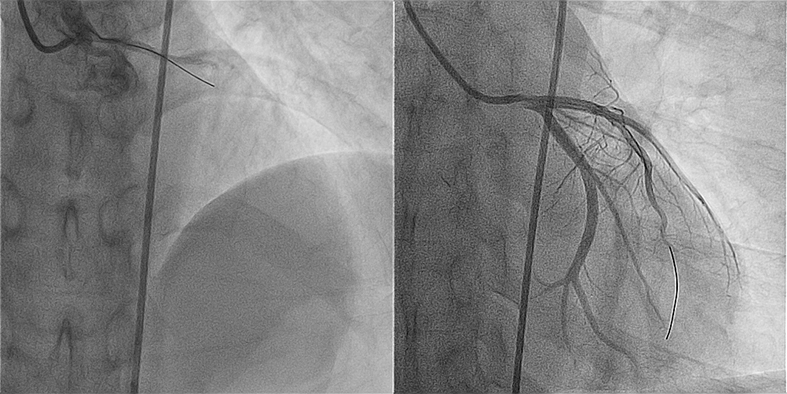

冠脉造影提示果然是急性前降支闭塞!“JL4.0、SION导丝、2.5的球囊、压力泵……”胡国勋主任根据病变情况,做出精准判断,介入团队紧张有序的进行手术。

随着球囊、支架穿过患者冠脉病变处,闭塞血管成功恢复3级前向血流,患者各项生命体征趋于稳定,终于转危为安。

18px;">▲左图为LAD闭塞影像、右图为支架术后影像